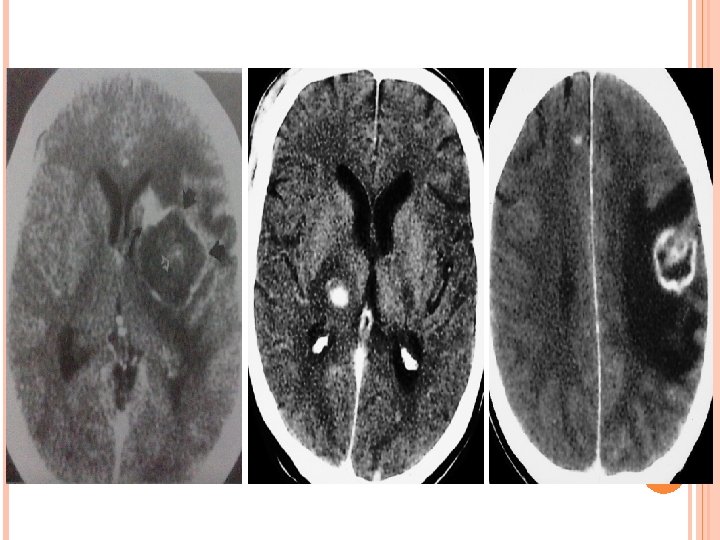

TOXOPLASMOSIS Infection by parasite T. gondii, present as altered sensorium, headache and mild hemiparesis. Multifocal involvement more common than solitary. Typically Supra-tentorial. Corticomedullary junction , Basal Ganglia, Thalamus, Intraventicular. Necrotising abscess. D/D-Lymphoma.

TOXOPLASMOSIS CT Plain CT – iso to hypodense with edema. CECT – no enhancement, minimal, ring or nodular enhancement. MRI T 1 WI – Iso to Hypointense but occasionally hyperintense due to hemorrhage which differentiate it from lymphoma. T 2 WI – Hypo- to isointense and are surrounded by high-signalintensity vasogenic edema. T 1 W+C—Ring or nodular enhancement with sometimes an eccentric mural nodule (eccentric target sign).

CRYPTOCOCCOSIS • Most common fungus to involve brain. • Common symptoms-Headache, blurring of vision and seizure. Cryptococcal meningitis: Widened subarachnoid space by mucoid material & thickened leptomeninges. Perivascular space involvement : M/c in HIV. Expanded perivascular spaces by gelatinous material in BG, midbrain, dentate nucleus and subcortical WM. Cryptococcomas: Conglomeration of cryptococci & mucoid material.

CRYPTOCOCCOSIS Imaging features: NECT-Sometimes hypodensity in BG. CECT-No enhancement. MR-Pseudocysts are hypointense on T 1 W images and hyperintense on T 2 W images suppress on FLAIR. No enhancement on T 1 W+C is typical although mild pial enhancement is sometimes present. D/D-Enlarge PVS, toxoplasmosis and TB.